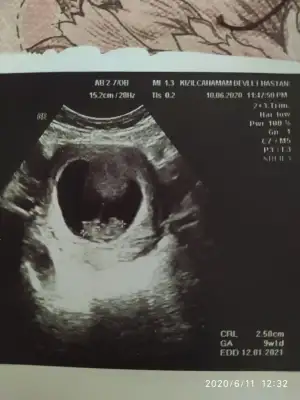

Merhaba biz bugün cinsiyetimizi öğrendik erkek dedi doktor Allah’ımın izniyleNubu kız görünüyor kafa şekli erkek görünüyorpozisyon değiştirmiyorsa nubu kız gibi

dr soylemeden siz gorun genital nub teorisi ( bebegin cinsiyeti)

Kimler kimler yazdı?Selam doğru tahmin erkek dedi doktor bugünErkek gibi

Evet net değildi kafa şekli erkek dedim ikisinin arasında kaldımMerhaba biz bugün cinsiyetimizi öğrendik erkek dedi doktor Allah’ımın izniyle

Başka usg varsa paylaşın sanki kız emin olamadımMerhaba bebeğimiz göstermedi bize cinsiyetini donuverdi arkasını 12+3 haftalık bi tahminde bulunabilir misiniz

Nacizane tavsiyem kendinizi şartlandırmayın arkadaşlar. Nub teorisine göre kız dedi benimkine bi arkadaş. Kese fotoğrafına da kız dendi. Bende çin takvimi ve karbonat testi tuttu erkek gösteriyodu  ve hissiyatım yanılmadı. İlk günden beri erkek hissediyorum. 16.haftalık olmadan kesinlikle kesinleşmiyo cinsiyet. 14.haftada kız gibi dedi doktor. Bi hafta sonra başka bi doktor erkek dedi. Ve sonra kesin erkek dedi.